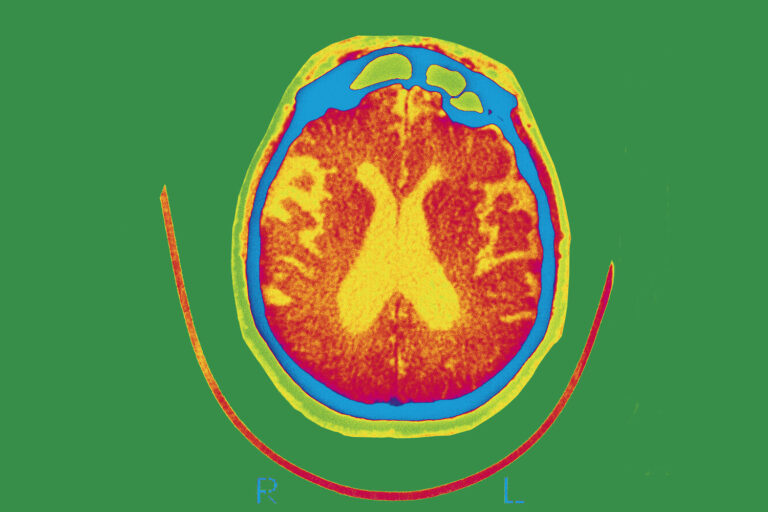

The FDA approved a new Alzheimer’s drug that has been shown in clinical trials to modestly slow...